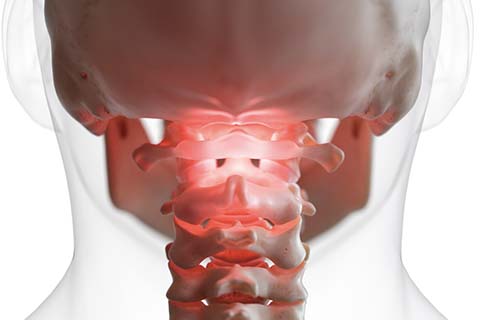

• 목디스크

목디스크는 경추(목뼈) 사이의 디스크가 빠져나오거나 뼈 조직이 비정상적으로 자라 목으로 지나가는 척추신경을 압박하여 통증이 발생하는 질환입니다.

목디스크 치료방법

• 비수술적 치료 물리치료, 운동치료, 약물치료, 주사치료, 신경성형술, 고주파수핵감압제거술

• 수술적 치료 현미경디스크제거술, 인공디스크치환술, 척추유합술

• 경추관협착증

주로 허리에 많이 발생하는 척추관 협착증이 경우에 따라 경(목)에서 나타날 수 있으며 심할 경우 목부터 다리까지 전신에 증상이 나타날 수있으므로 각별한 주의가 필요한 질환입니다.

• 경추척수병증

중추신경인 척수를 직접 압박하여 증상이 나타나는 질환입니다.

• 거북목증후군

잘못된 생활습관으로 목의 곡선이 일자로 또는 역C자 형태로 변형된 상태를 거북목 증후군이라 합니다.

• 후종인대골화증

후종인대가 유전적 이상, 외상, 타질환 등의 원인에 의해 두터워지고 뼈처럼 딱딱해져 각종 증상을 일으키는 상태를 말합니다.